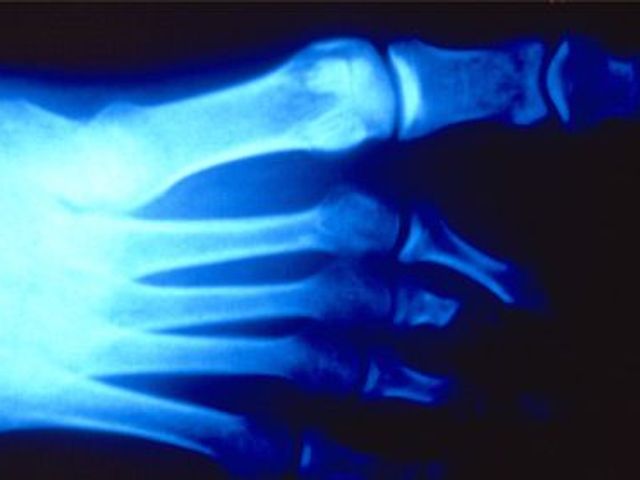

Auch wenn längst keine Narben mehr zu sehen sind: Röntgenaufnahmen verraten ein Leben lang, was Folter anrichten kann. Seit 30 Jahren sammelt ein deutscher Arzt die Dokumente des Grauens.